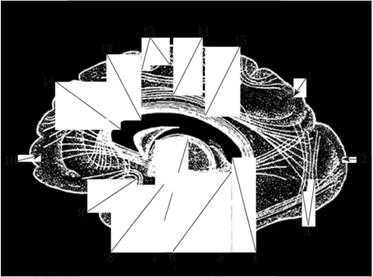

Рис. 3.28. Расположение проводящих путей во внутренней капсуле:

1 - корково-стриарный путь; 2 - чечевицеобразное ядро; - лобно-мостовой путь; 4 - корково-ядерный путь; 5 - корково-спинномозговой путь; 6 - таламо-корковый путь; 7 - затылочно-височно-мостовой путь; 8 - слуховая лучистость; 9 - зрительная лучистость; 10 - таламус; 11 - головка хвостатого ядра

Колено внутренней капсулы занимает корково-ядерный путь. Заднюю ножку образуют корково-спинномозговой путь, таламо-корковый путь, затылочно-височно-мостовой путь, затем располагаются волокна, происходящие из ядра медиального коленчатого тела - слуховая лучистость (коленчато-височный путь) и, наконец, волокна из ядра латерального коленчатого тела - зрительная лучистость (коленчато-шпорный путь).